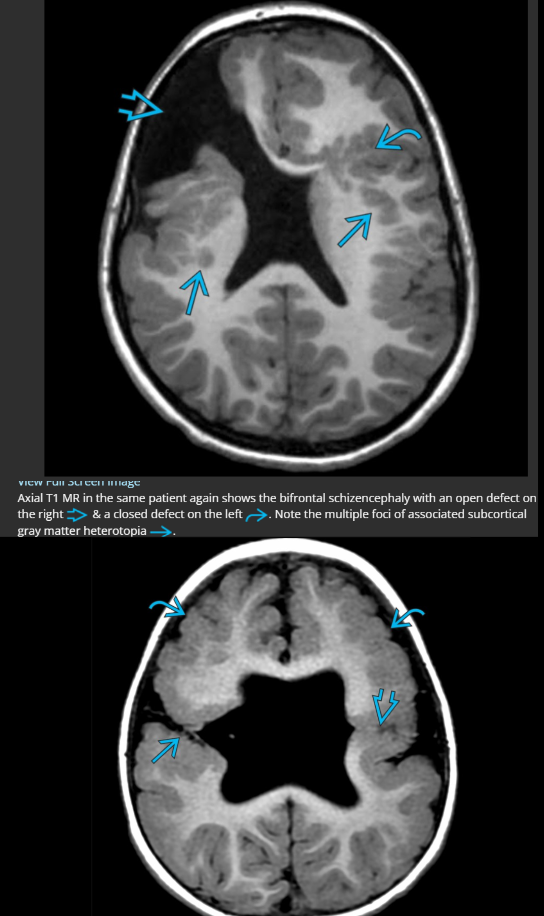

What are the types of schizencephaly and list 2 associated abnormalities

“Transmantle” (aka ext from cortical surface of brain to the ventricles - ie pia to ependyma) cleft lined by grey-matter (GM)

1. Open lip - cleft has clear CSF space separating 2 sides

2. Closed lip - no clear CSF space, cleft walls closely opposed (better prognosis)

Associations:

* Associated abnormalities

* GM heterotopia adjacent to cleft

* Contralateral polymicrogyria

* Absent septum pellucidum (esp if bilateral clefts)

* Septo-optic dysplasia